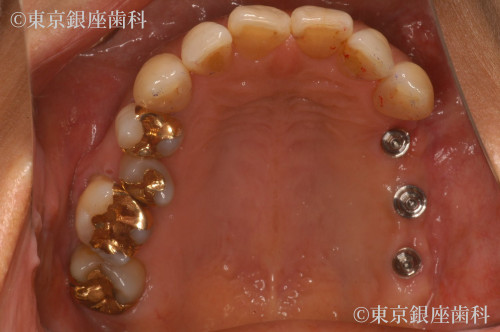

左上奥歯の骨の厚みが薄かったため、骨造成を併用した3本の部分インプラント治療

Before

After

歯周病がひどく悪化し、動揺も激しくなった左上奥歯三本の歯を紹介元のクリニックの診断と同様、抜歯する必要がありました。歯科治療に対する恐怖心がとても強く、また抜歯の経験がなかったため、静脈内鎮静を併用しての治療を計画しました。歯を抜いた後、およそ5ヶ月の間に、骨が回復する期間を設け、その後歯科インプラント手術を予定しました。上顎左側、奥歯の骨の厚みが薄く、インプラントが固定される骨量が不足していたため、上顎洞内に骨を足す治療(以下サイナスリフトと呼ぶ)を併用し、三本のインプラントを埋入する計画を立てました。また抜歯後およびインプラント体と骨が結合するまで6か月の治癒期間中は、食事が不自由しないように、仮の義歯を作製し使用してもらう計画を立てました。

上顎左側の奥歯は、歯周病の進行が激しく、顎の骨の吸収がとても大きいことが認められました。上顎洞までの骨の量が不足していたため、サイナスリフトを併用したインプラント手術が必要でした。抜歯後およびインプラント体と骨が結合するのを待つ期間中に仮の入れ歯を装着してもらいましたが、患者様の術前当初のお話しにあったように違和感があり、インプラントでの口腔機能回復を選択してよかったとのお言葉を頂きました。また抜歯やインプラント手術などの外科治療時には。静脈内鎮静を併用して治療に臨めたので、歯科に対する恐怖心が和らいだとの事でした。現在、経過順調に定期健診を受診されておられます。